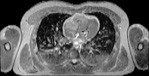

NMR

Pd                          / T2 \                         T1